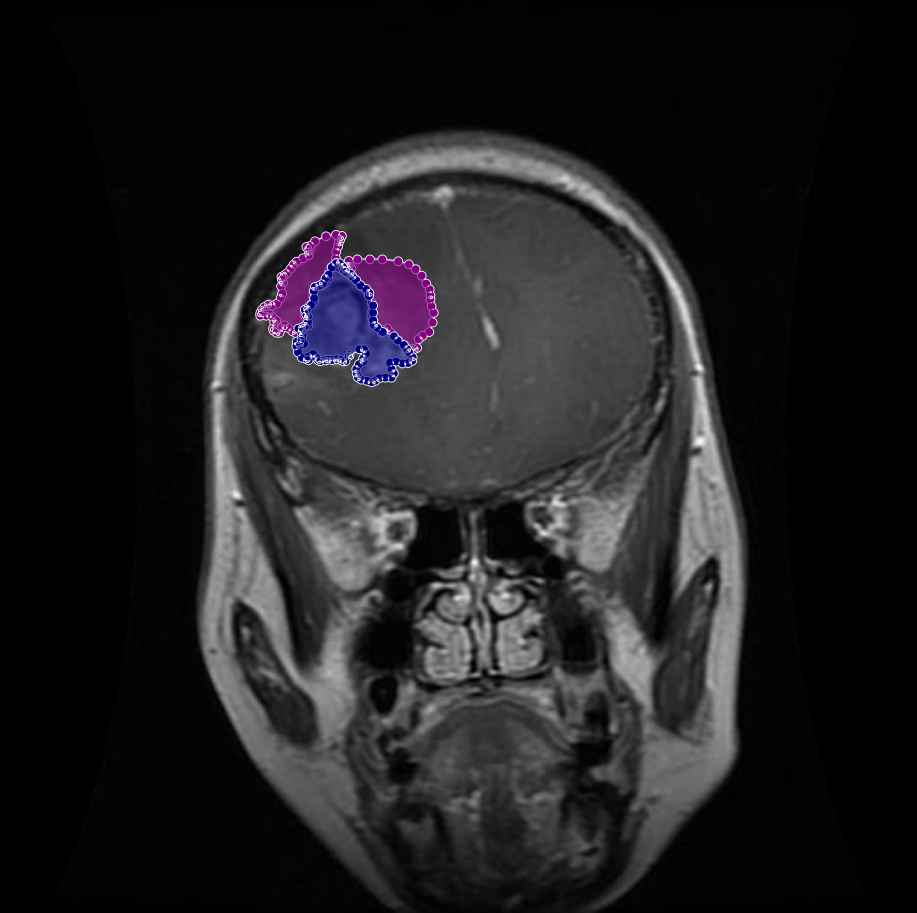

Figure 6: Samples of partial-region overannotations. The red area indicates regions that were initially marked as tumorous but were later identified by the radiologist and physician as non-tumorous.

In other instances, certain areas that were mistakenly included as part of the tumor region were refined based on radiologist and physician feedback. These areas, though visually similar to tumor tissue, were determined to be non-tumorous upon closer examination. As illustrated in Figure 6, the removal of these incorrect segments resulted in more precise tumor masks and enhanced the reliability of the dataset.